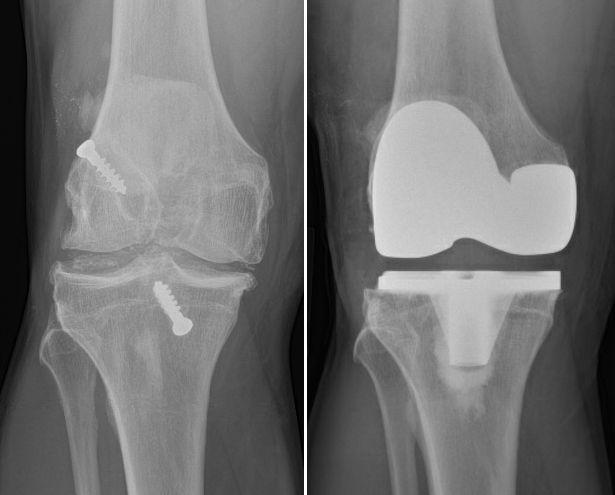

JOINT REPLACEMENT / ARTHOPLASTY

Advanced knee arthritis – left image,

Total knee replacement – right image